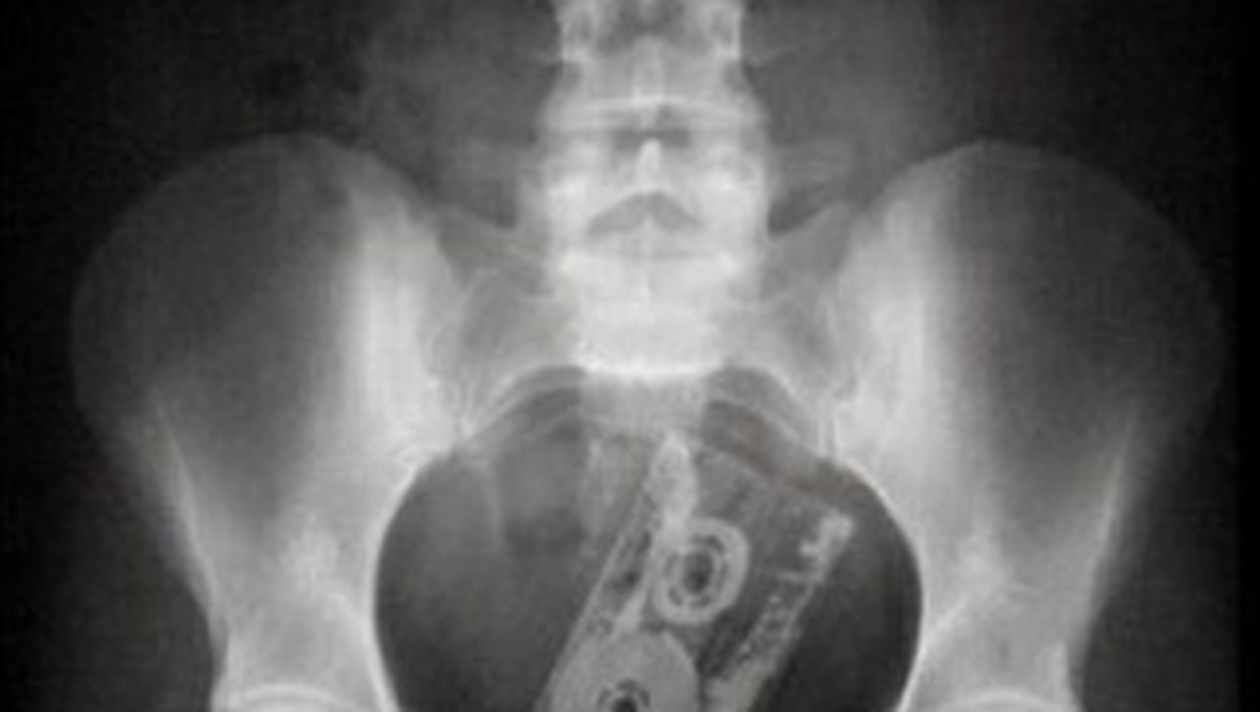

Un grup de medici a hotarat ca obiceiurile ciudate ale oamenilor care isi introduc in rect tot felul de lucruri trebuie impartasit cu cei care nu fac asta. Asa a aparut pe piata o carte cu radiografii neobisnuite.

Psihiatrul Marty A. Sindhian, psihiatrul Rich E. Dreben si medicul Murdoc Knight au prezentat in cartea „Stuck Up” (Blocat) 100 de astfel de cazuri.

Printre obiectele ramase blocate in corpurile pacientilor- de obicei in rect, dar si in esofag sau uretra- se numara o caseta audio, o pereche de ochelari, un stecher sau o papusa Barbie.

„Casetele audio nu mai sunt atat de populare, in ziua de azi, asa ca nu ma astept sa mai apara in radiografii. Dar cineva a ajuns la urgente cu un iPod inauntru, ceea ce arata ca si moda in ceea ce priveste obiectele care raman blocate intr-o persoana evolueaza”, a explicat Sindhian.